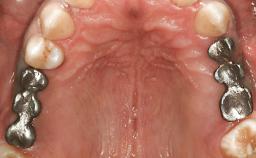

German Gallucci

My ITI - German Gallucci